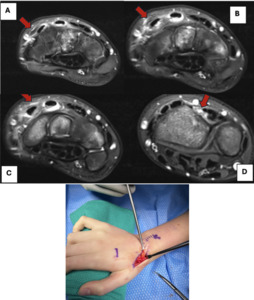

X-rays were obtained three and six weeks after the initial injury to monitor the healing of the fracture. She was discharged from treatment and regained full wrist function, reporting no lingering symptoms. Ten weeks after her intimal injury, she returned, reporting a sudden inability to extend her right thumb fully; no additional trauma or inciting event was reported. On physical exam she could not perform retropulsion or extend her thumb at both the metacarpophalangeal (MCP) and interphalangeal (IP) joints. Magnetic resonance imaging (MRI) was obtained demonstrating EPL tendon rupture [Figure 2 A-E]. The patient was also noted to have an EIP tendon on MRI. The patient was fitted with a thumb Spica brace and scheduled for surgery.

EPL tendon rupture can be diagnosed through a physical exam and confirmed with MRI. Patients will exhibit limited thumb extension at the IP joint and possible deficiencies at the MCP joint. Additional findings of loss of thumb retropulsion and a possible visible deformity where the EPL tendon runs along the dorsal aspect of the wrist may be encountered.5 A ruptured EPL tendon is best seen on axial wrist MRI, where it is noted to be absent at the level of Lister’s Tubercle and appears irregular and fragmented just ulnar to the tubercle.10 However, the EPL tendon can be difficult to track on MRI, and the angle made between the plane of imaging and the orientation of the tendon can alter the signal intensity; a “magic angle” of 55 degrees has been identified at which signal intensity is highest and can be mistaken for tendon pathology.11 EPL tendon rupture post distal radial fracture is most commonly treated with EIP tendon transfer because rupture often occurs secondary to tendon attrition with resulting frayed ends, making primary repair less feasible. Primary tendon repair is applicable in acute rupture of the EPL tendon due to direct trauma, as seen following a laceration.12 96.5% of patients have an EIP tendon. In those that do not have an EIP tendon, tendon grafting, usually involving the palmaris longus tendon, can be used to repair the EPL.12 This procedure is often not preferred, given its increased difficulty and risks.